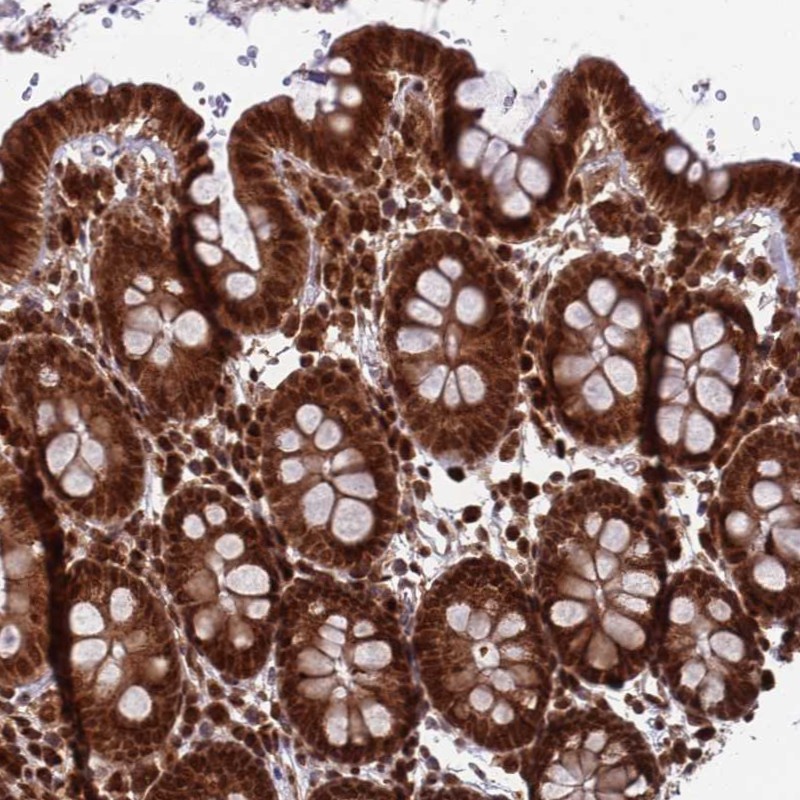

Immunohistochemical staining of human colon shows strong cytoplasmic and nuclear positivity in glandular cells.